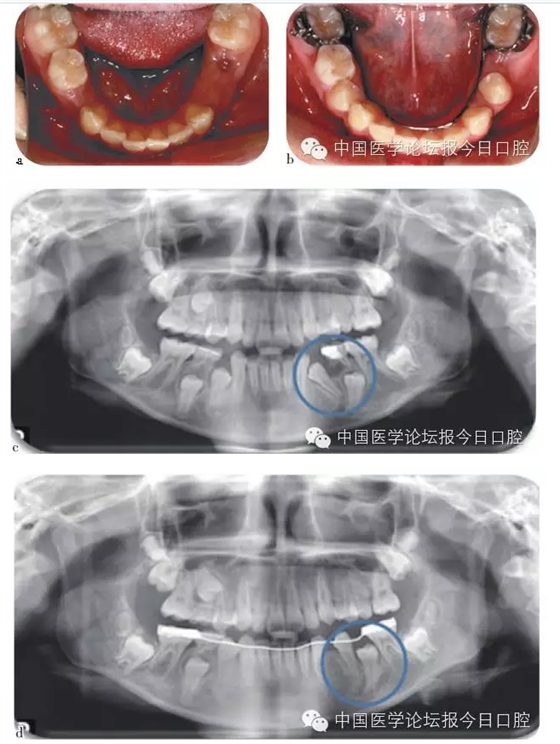

如病例一(圖1)所示,75深齲,34牙胚萌出異常,拔出75,行舌弓間隙維持后,34萌出道自行調(diào)整和萌出。

圖1 75深齲,34牙胚萌出異常,拔除75,舌弓間隙維持后,34萌出道自行調(diào)整萌出